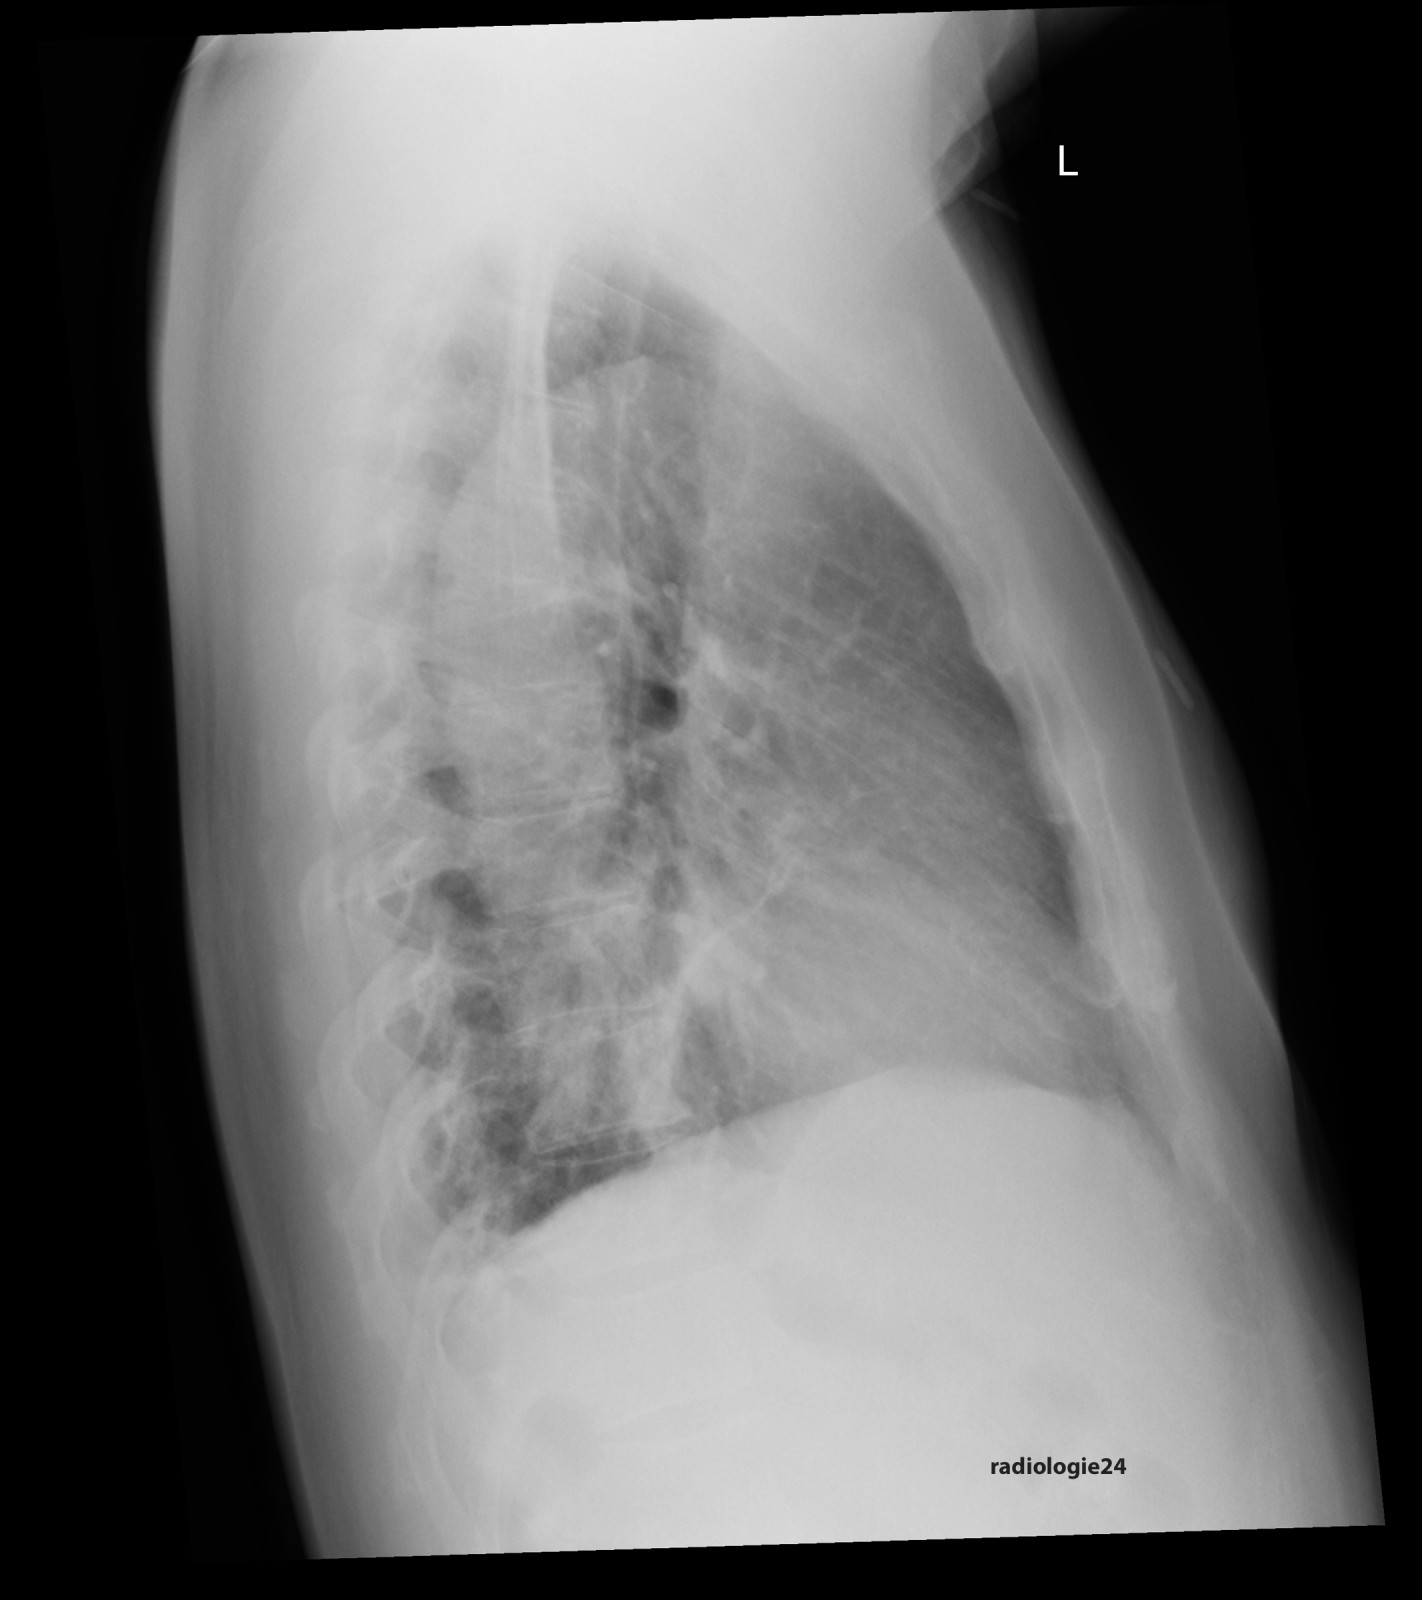

Link zur Auflösung mit ausführlichem Befund

https://www.radiologie24.ch/radiologie-mediathek/roentgenfall_des_monats